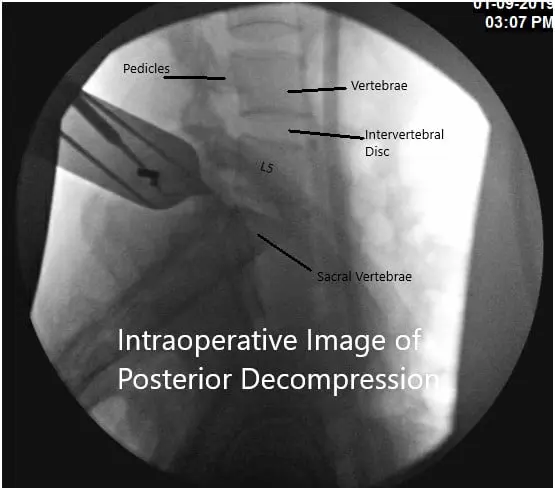

Intraoperative fluoroscopic image

Intraoperative fluoroscopic image.

Preoperative antibiotics were dosed and fluoroscopy was used to localize our incision using a spinal needle inserted at the L5-S1 disk interspace. A #10 blade was used to incise the skin in the midline over the L5-S1 interspace down to the level of the subcutaneous fat.

Thereafter, Bovie cautery was used to continue the dissection along the left laminae of L5 and S1 exposing the interspace.  We used a Taylor retractor to hold the muscle and skin edges apart.  Using fluoroscopy once again, we confirmed our level of operation.  A high-speed electric drill was used to create a foraminotomy at L5 and S1 in order to expose the epidural space.